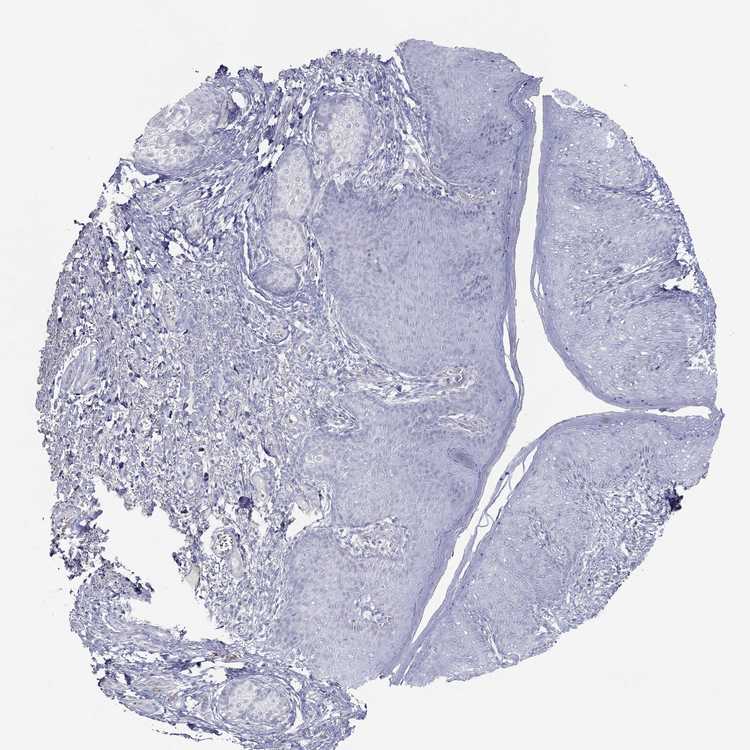

SKIN 1 - Antibody stainingi

Antibody staining in the annotated cell types in the current human tissue is reported as not detected, low, medium, or high, based on conventional immunohistochemistry profiling in selected tissues. This score is based on the combination of the staining intensity and fraction of stained cells.

Each image is clickable and will lead to virtual microscopy that enables deeper exploration of all samples and also displays staining intensity scores, fraction scores and subcellular localization as well as patient and tissue information for each sample.

Antibody HPA079265

Langerhans Not detected

Fibroblasts Not detected

Keratinocytes Not detected

Melanocytes Not detected

SKIN 2 - Antibody stainingi

Epidermal cells Not detected